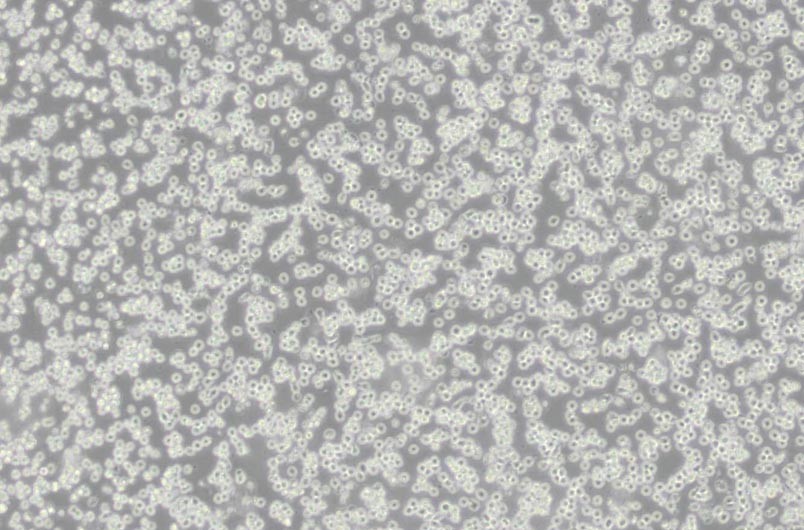

細(xì)胞形態(tài) : 淋巴母細(xì)胞樣

生長特性 : 懸浮細(xì)胞